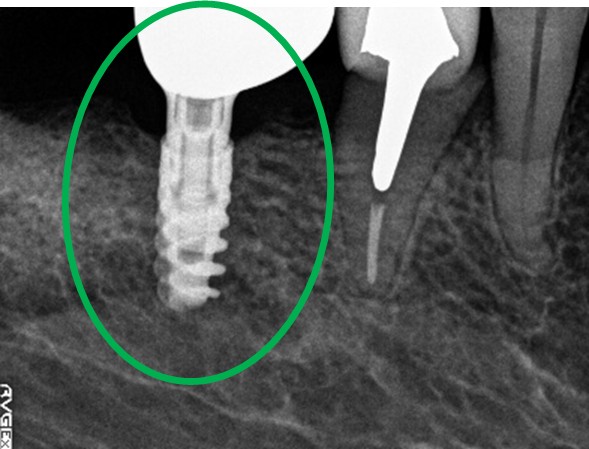

右下のブリッジの支台になっている後方の歯が、歯根破折を起こしていましたので抜歯しました。インプラントを右下第一大臼歯部に1本埋入しました。

所感

右下のブリッジの支台になっている第二大臼歯が歯根破折を起こしていました。抜歯後欠損を補う方法には部分入れ歯かインプラントがあります。もし部分入れ歯を選択されていましたら、初めての入れ歯で自分の歯と同じ感覚で噛むことができないので、おそらく使わない入れ歯になっていたことが、想像できます。2本欠損でしたが、1本だけの埋入を希望されました。インプラントは、欠損を補う最良の方法と考えます。

インプラント1本:¥363,000(税込)

Before

抜歯後

After